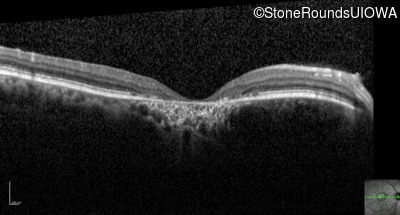

Optical Coherence Tomography - Left - 20/125 -2

Exemplar / OCT Stack